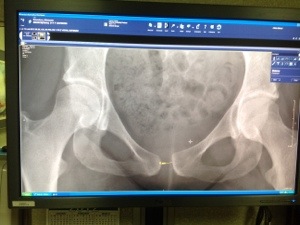

I just realized that I haven’t posted my before and after x-rays! I had a long, busy and happy day and I’m worn out so I’ll stick to these pictures for now and explain more later.